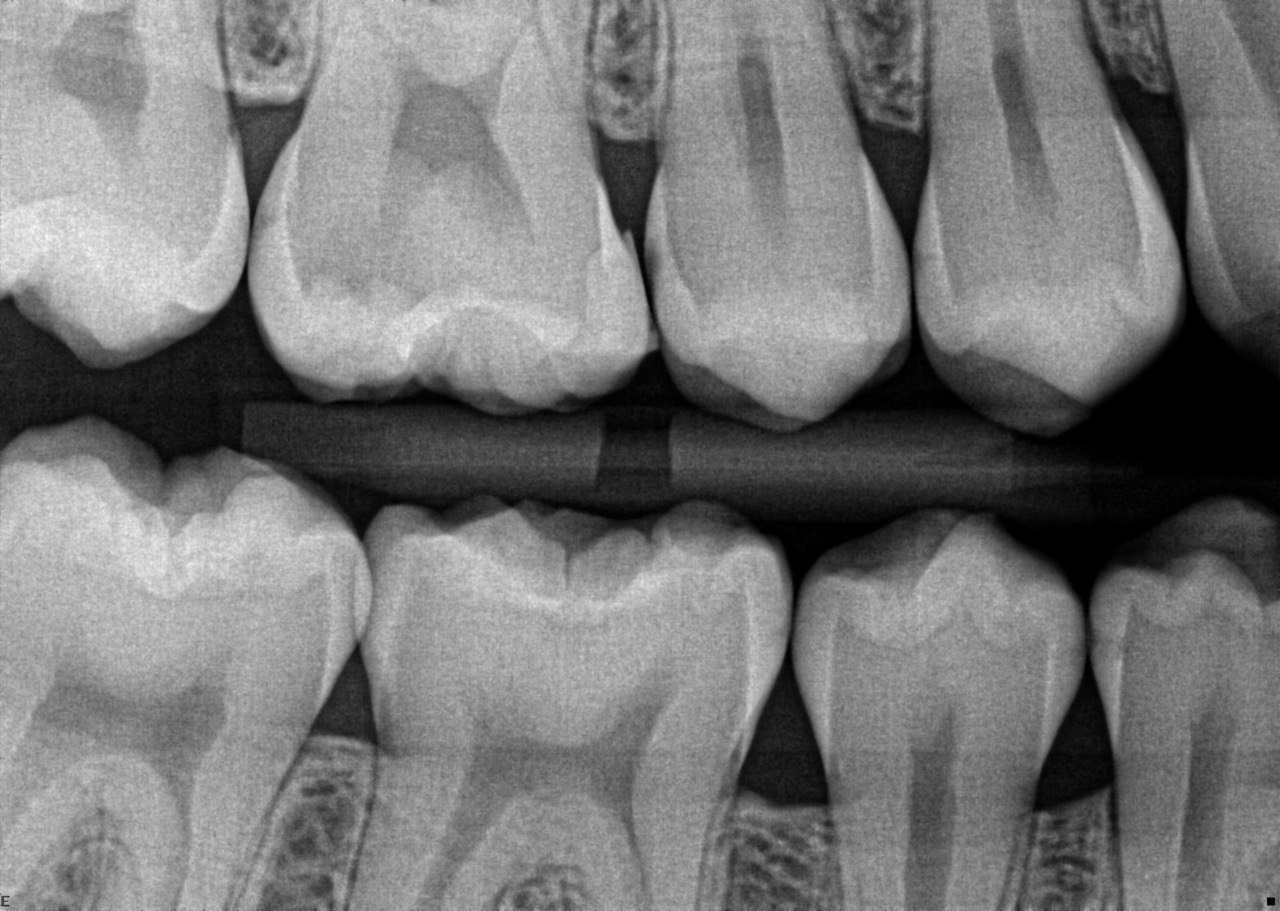

2. What surface require restoration?